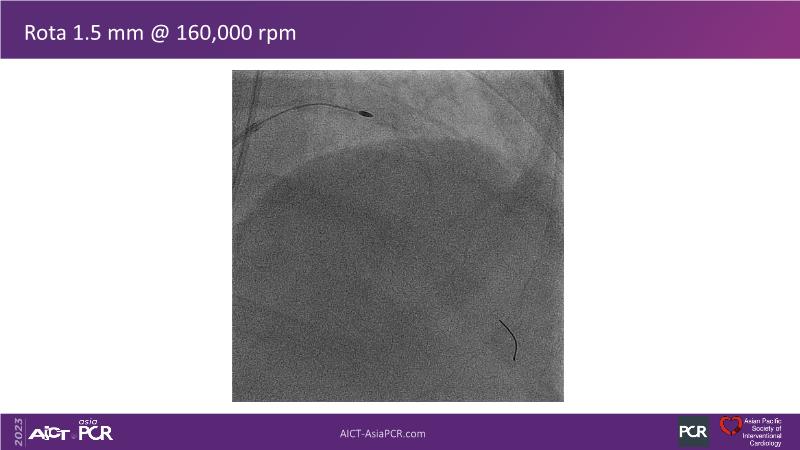

This session is recommended for you if you are seeking insights into the advantages of using IVUS imaging over visual assessment for better outcomes in left main bifurcation procedures. Discuss with experts the benefits of using RotaCUT in lesion preparation for left main bifurcation and explore the impact of high radial strength stents on the procedure's success.

• To see advantages of RotaCUT as part of lesion preparation in left main bifurcation